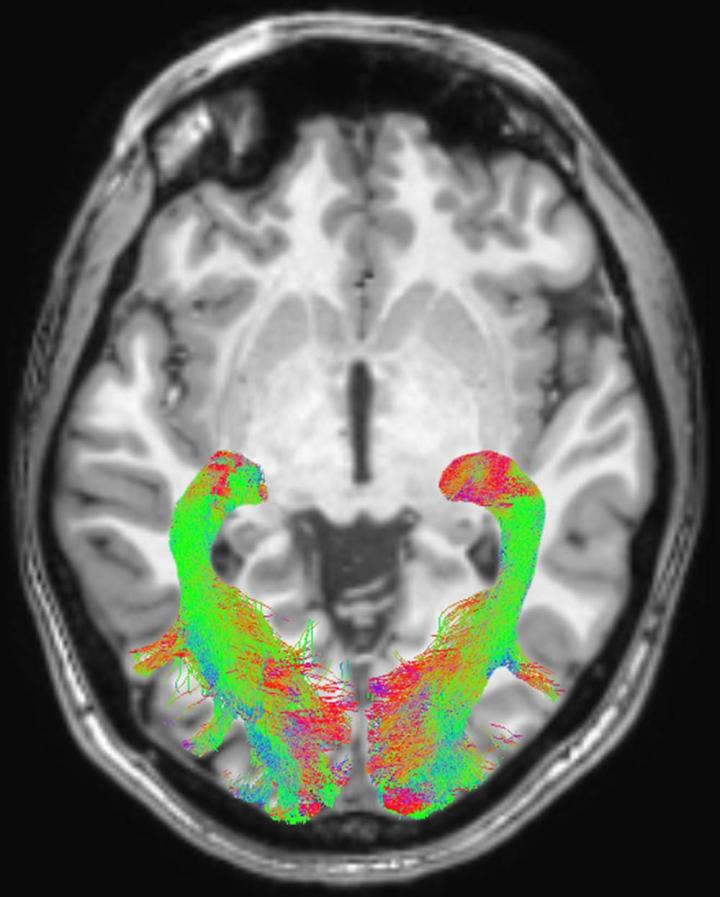

Figure 1 Left and right Optic Radiation

image: Left and right optic radiation (OR) image in a representative subject overlaid onto a T1-weighted axial volume image of the same subject. OR images were obtained on the basis of diffusion-weighted volume images by means of constrained spherical deconvolution fitting and related tractography. Each bundle was automatically colored according to tract main directionality: red for left to right, green for anterior to posterior, and blue for inferior to superior. view more

The researchers found significant abnormalities within the visual system brain structures of Parkinson's disease patients, including alterations of optic radiations, a reduction of white matter concentration and a reduction of optic chiasm volume. The optic chiasm is the part of the brain where the left and right optic nerves intersect.